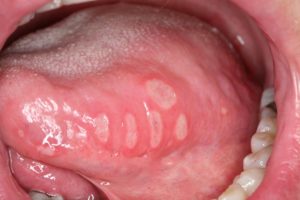

Aphtose

Même limité au volet médical, la stomatologie constitue un vaste domaine comportant de nombreuses affections, plus ou moins fréquentes. Le plus souvent, elles sont spécifiques de la cavité buccale (infections bactériennes ou virales, kystes d’origine dentaire, manifestations liées à des parafonctions, paresthésies, tumeurs bénignes, cancers…) mais certaines sont en rapport avec une affection cutanée (lichen plan, maladies bulleuses …) ou avec une affection systémique (hémopathies, maladies auto-immunes…).